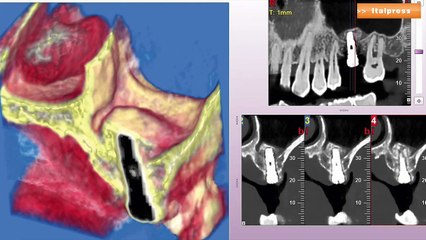

Convegno di diagnostica per immagini radiologiche

Convegno di interventistica radiologica svoltosi ad Andria.